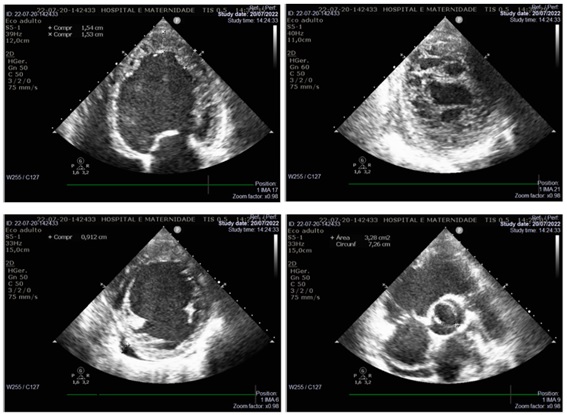

Ecocardiograma transtorácico (Figura 2): átrio esquerdo de 45 mm, ventrículo esquerdo com espessura miocárdica reduzida, com hipertrabeculação acometendo mais que 2/3 da espessura miocárdica, situadas em ápice e segmento médio e apical das paredes lateral e inferior, fração de ejeção de 26,53%. O ventrículo direito apresentou espessura miocárdica normal, com hipocinesia difusa e hipertrabeculação em região do ápice. Pressão sistólica em artéria pulmonar de 46 mmHg.

O exame complementar mais utilizado para o diagnóstico é o ecocardiograma transtorácico. O critério mais importante é em relação à camada trabeculada, que deve ter uma relação MNC/miocárdio compactado >2. Achados de disfunção sistólica e diastólica fortalecem o diagnóstico.